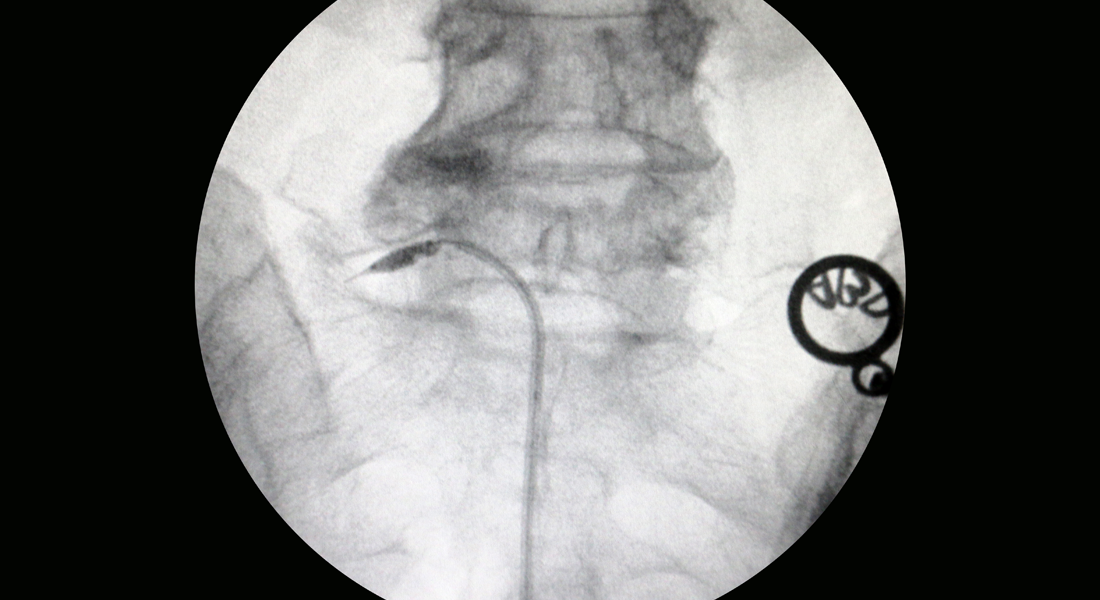

특수 카테터로 좁아진 척추관을 확장시켜 치료하는 비수술 요법

추간판 탈출로 신경이 압박되는 부분에 풍선 확장 기능이 포함된 특수 카테터를 이용하여 주변을 확장시켜 압박을 해소하고 통증을 없애는 치료법입니다. 확장과 함께 증상 호전에 도움이 되는 약물을 주입하여 효과적으로 통증을 완화할 수 있습니다.